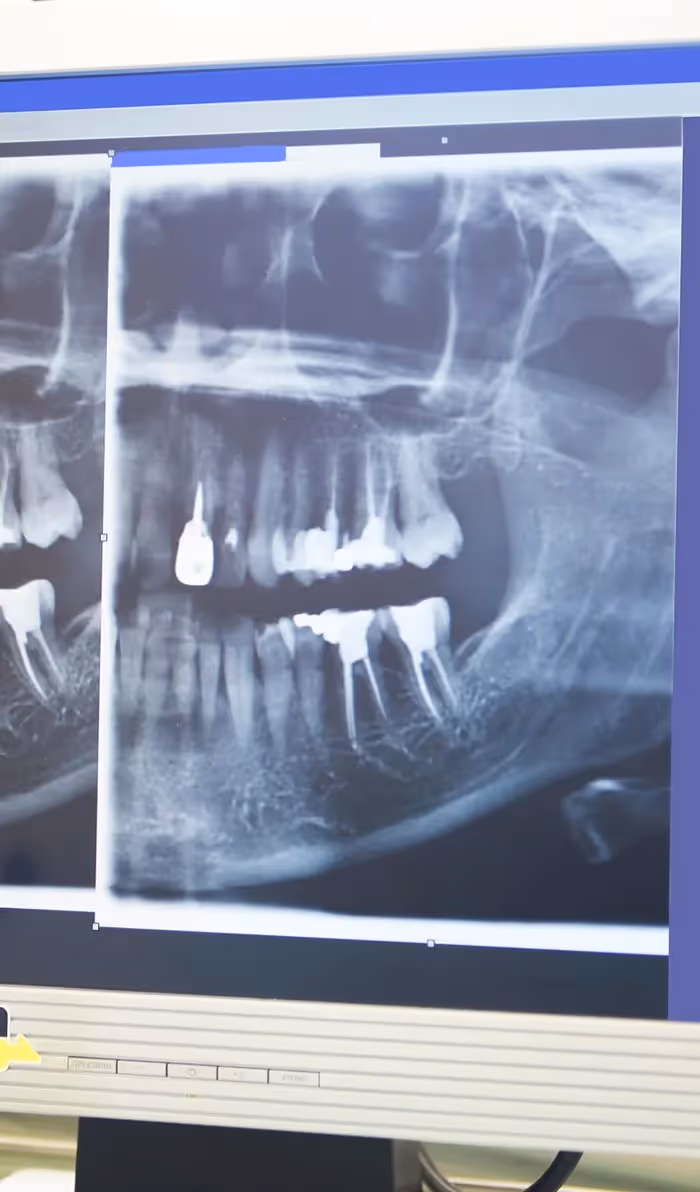

Digital Imaging

Advanced digital imaging techniques have taken the guesswork out of root canal therapy, resulting in a quicker, more efficient procedure with less pain and discomfort than ever before.

Your dentist will begin with a comprehensive examination of your tooth and x-rays to identify the cause of your dental discomfort. If an infection is present, they'll assess its severity to determine if a root canal is the appropriate treatment option. If root canal therapy is necessary, your dentist will ensure the treatment area is completely numb, including the nerves.